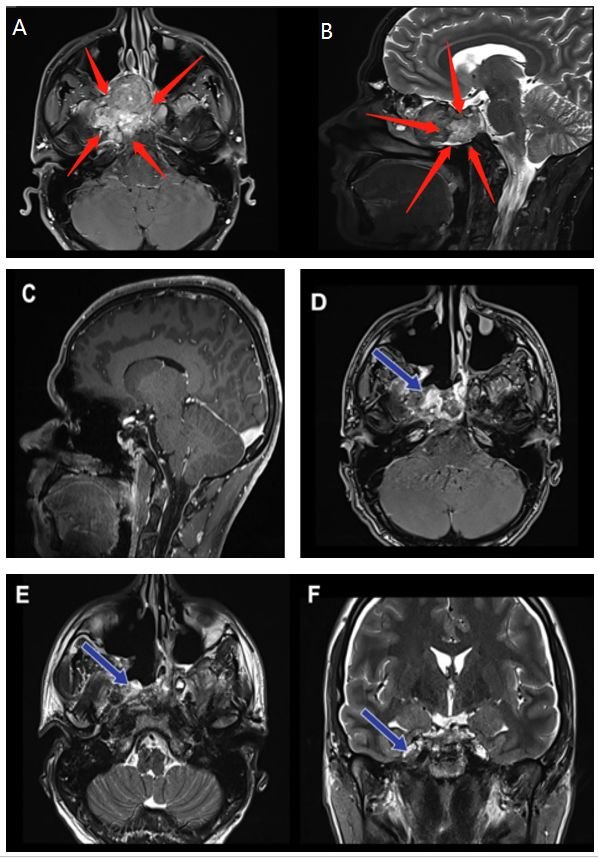

術(shù)前(紅色箭頭):A、B圖顯示位于右海綿竇中心的脊索瘤病變。病變集中在右側(cè)海綿竇和翼骨上,并在右側(cè)鄰卵圓孔。

術(shù)后(藍(lán)色箭頭):C圖表示矢狀位顯示無(wú)腫瘤殘余。D、E、F圖顯示軸位、冠狀位脊索瘤被絕大部分切除。